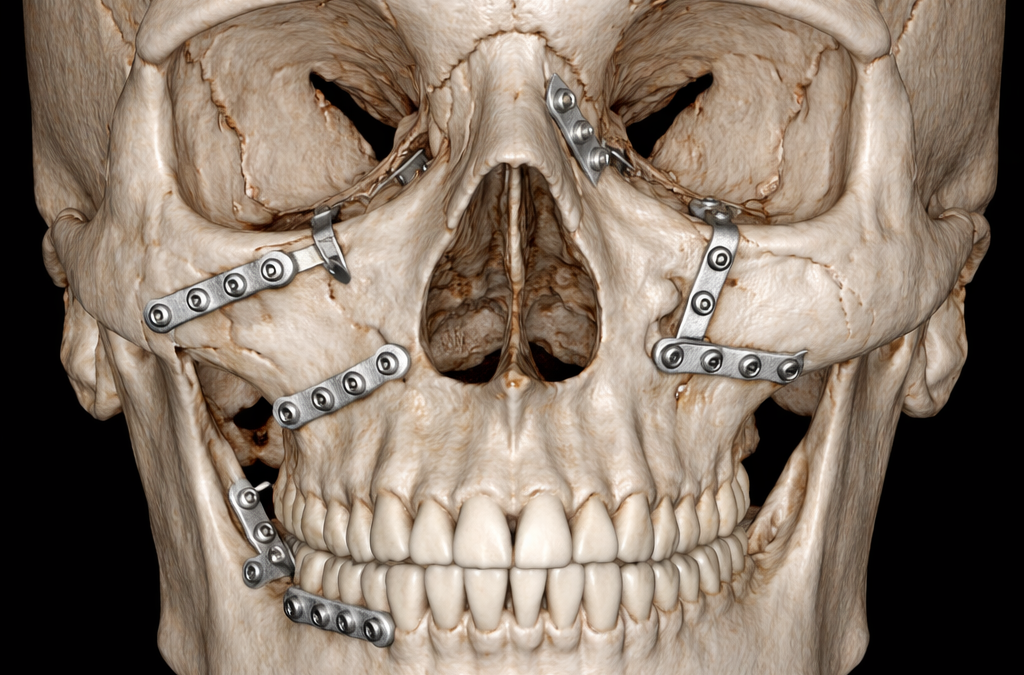

Trauma Case Report – Apr 22, 2025

Gunshot suicide and the interdisciplinary management of a complex craniofacial injury: A case report and review of literature

Yildirim A., Hertach R., and Yildirim V.

Suicide ranks among the causes of death in industrialized nations. The authors present a case demonstrating how a firearm-related suicide attempt can be effectively managed and how long-term quality of life may be significantly improved through appropriate medical and psychological intervention.